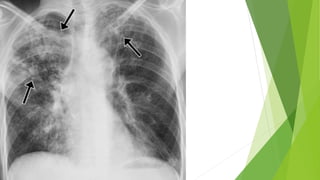

 Radiological : Chest x-ray and CT scan of chest

Investigation  Radiological :Chest x-ray and CT scan of chest  Sputum examination: AFB stain At least two sputum samples (including at least one obtained in the early morning)  Sputum Culture  Pleural fluid Examination: ADA(adenosine Deaminase)  Xpert MTB/Rif (Nucleic acid amplification test NAAT)  Bronchoscopy  Tuberculin skin test :  Baseline Blood tests: CBC, CRP, ESR, Urea, and electrolytes, LFT